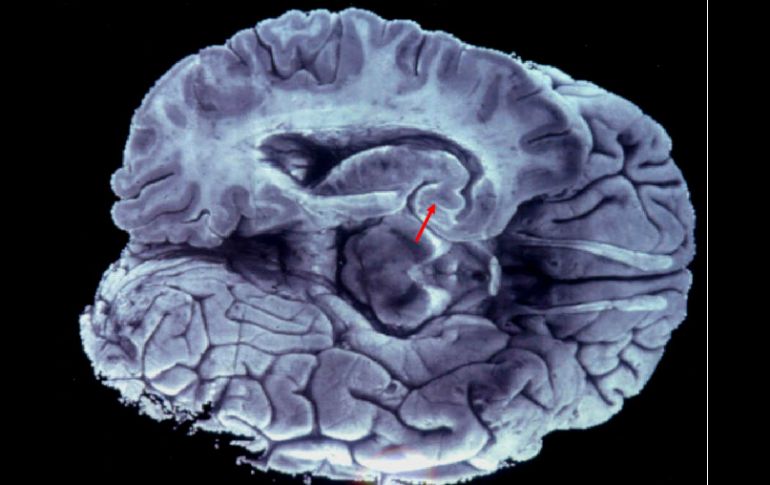

Al confiarle todo a la tecnología, estamos dejando espacios en nuestro cerebro que podrían utilizarse en actividades intelectuales. ARCHIVO /